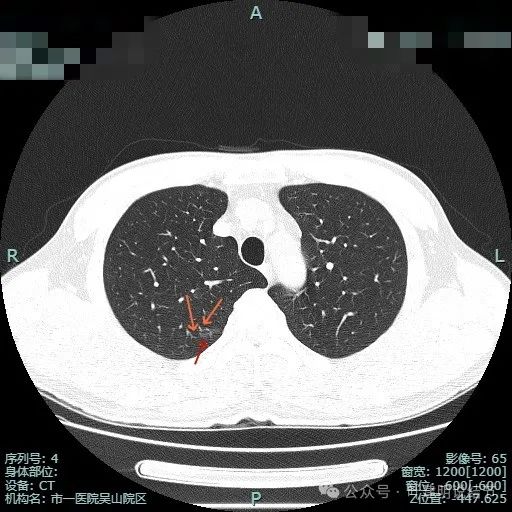

病史摘要:患者主因“检查发现肺部阴影5年”就诊。5年前当地医院体检胸部CT提示肺部结节,无明显症状未治疗。2024年11月杭州市肿瘤医院复查胸部CT,右肺多枚小结节,LUNG-RADS 2,建议年度随诊。现患者无不适,为求进一步诊治入院。起病以来,患者神志清,精神、胃纳、睡眠、二便正常,体重无明显变化。诊疗过程:体格检查未提及。多次胸部CT显示右下叶磨玻璃结节,轮廓与瘤肺边界清楚,

肺不典型增生

典型